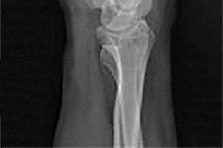

Question 36:

A 5-year-old child falls on an outstretched hand and sustains the elbow injury shown. The fracture is displaced 4 mm. If left untreated or mismanaged as a simple sprain, what is the most likely long-term clinical complication?

Options:

- Cubitus varus and tardy radial nerve palsy

- Cubitus valgus and tardy ulnar nerve palsy

- Myositis ossificans of the brachialis

- Premature closure of the olecranon apophysis

- Volkmann's ischemic contracture

Correct Answer: Cubitus valgus and tardy ulnar nerve palsy

Explanation:

The scenario describes a lateral condyle fracture of the pediatric humerus. Because the lateral condyle provides the lateral buttress of the elbow and is intra-articular, nonunion (due to inadequate immobilization or failure to fix a displaced fracture) commonly leads to a progressive cubitus valgus deformity. Over time, the increased carrying angle stretches the ulnar nerve behind the medial epicondyle, resulting in a tardy ulnar nerve palsy.